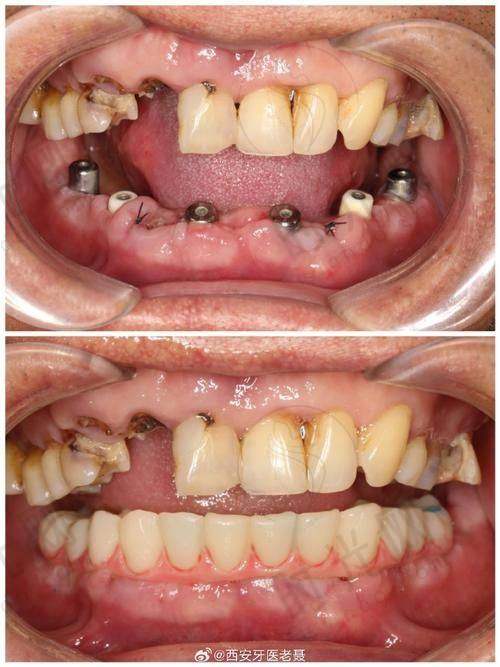

3. 松动牙固定:给牙齿“搭支架”,适合二度松动

如果牙齿松动幅度较大(二度松动),单纯治疗炎症还不够,需要“外力固定”。就像盖房子时“加固横梁”,医生会用牙周夹板(一种类似牙冠的装置)把松动牙和旁边健康的牙齿连在一起,形成一个整体,让松动牙“借力”修复稳固。固定后3 - 6个月,牙周组织逐渐愈合,牙齿就能重新“扎根”。

适合人群:二度松动、多颗牙松动(如整排牙都晃)、正畸后暂时性松动。材料上有两种选择:可摘夹板(每天能取下清洁,适合中老年患者)和固定夹板(粘在牙齿上,不能取下,适合年轻人)。62岁的张阿姨就是用固定夹板固定了右侧3颗松动牙,3个月后复查,牙齿晃动幅度从1.5毫米降到0.5毫米,吃饭终于不疼了。